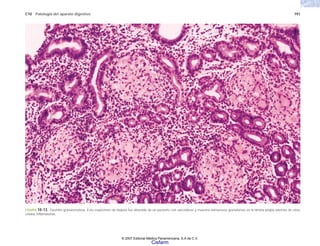

FIGURA 2-13. Histología de las vellosidades articulares en la artritis reumatoide. Hay proliferación de células sinoviales, infiltración inflamatoria y formación de pannus.